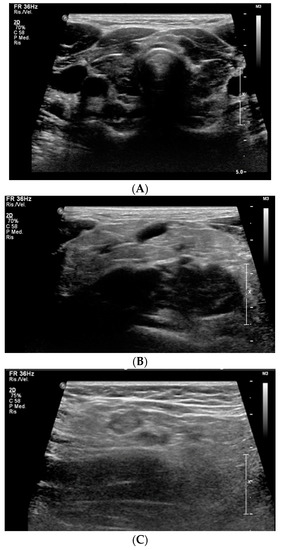

Pediatric Myxedema Due to Autoimmune Hypothyroidism: A Rare Complication of a Common Disorder

In children, hypothyroidism usually presents non-specific symptoms; symptoms can emerge gradually, compromising a timely diagnosis. We report the case of a 13-year-old male, who was admitted to the hospital due to swelling of the torso and neck. Besides these symptoms, the child was [...] Read more.

In children, hypothyroidism usually presents non-specific symptoms; symptoms can emerge gradually, compromising a timely diagnosis. We report the case of a 13-year-old male, who was admitted to the hospital due to swelling of the torso and neck. Besides these symptoms, the child was healthy, except for a significant growth delay. Ultrasound evaluation and blood tests led to the diagnosis of myxedema secondary to severe hypothyroidism, which was due to autoimmune thyroiditis. Further investigations revealed pericardial effusion and pituitary hyperplasia, with hyper-prolactinemia. Treatment with levothyroxine led to edema regression and clinical, hemato-chemical and radiological improvement. After 6 months, growth velocity increased, although the recovery of growth already lost was not guaranteed. Brain MRI showed regression of pituitary hyperplasia. The diagnostic delay in this case was probably due to the patient’s apparent good health, and the underestimation of growth restriction. This report underlines the importance of growth monitoring in adolescence, a critical period for identifying endocrine conditions; if undiagnosed, these conditions can lead to serious complications, such as myxedema in hypothyroidism, with potential effects beyond growth on multiple organs. Full article

Show Figures

Figure 1